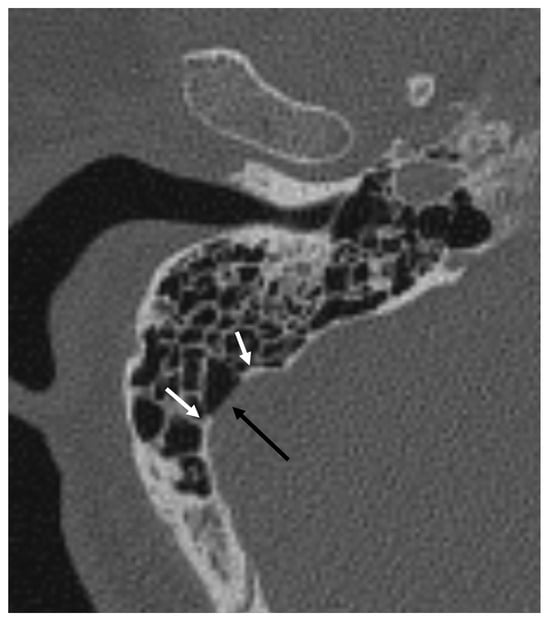

The Possible Relationship Between Sigmoid Dehiscence, Degree of Mastoid Pneumatization, and Sigmoid Sinus Position in Patients with Pulsatile Tinnitus

Objective: This study aimed to determine the relationship between sigmoid sinus dehiscence (SSD), sigmoid sinus topography, mastoid pneumatization, and adjacent temporal bone structures in patients with pulsatile tinnitus (PT). Methods: A retrospective analysis was performed on 344 temporal bone cone-beam computed tomography (CBCT) scans (172 PT patients and 172 age- and sex-matched controls). The degree of mastoid pneumatization, presence and size of SSD, sinus topography, and distances between the sigmoid sinus and key landmarks—the lateral semicircular canal (LSCC), jugular bulb (HJB), and external auditory canal (EAC)—were measured. Quantitative and qualitative characteristics were compared between groups, and independent predictors of PT were identified using multivariate logistic regression. Results: Compared to controls, SSD was substantially more common in the PT group (115/172 vs. 44/172, p < 0.001). Patients with PT had significantly larger anteroposterior and vertical sigmoid sinus dehiscence diameters (4.61 ± 0.99 mm vs. 3.87 ± 0.25 mm and 3.37 ± 0.47 mm vs. 2.92 ± 0.14 mm, respectively; both p < 0.01). Additionally, in the PT group, the sigmoid sinus was situated closer to the lateral semicircular canal, jugular bulb (JB), and external auditory canal (all p < 0.01). Conclusions: Venous pulsatile tinnitus was substantially correlated with sigmoid sinus dehiscence, sinus topography, and decreased sinus–EAC distance. Quantitative CBCT evaluation of these anatomical relationships could help with surgical planning and enhance diagnostic evaluation. Full article